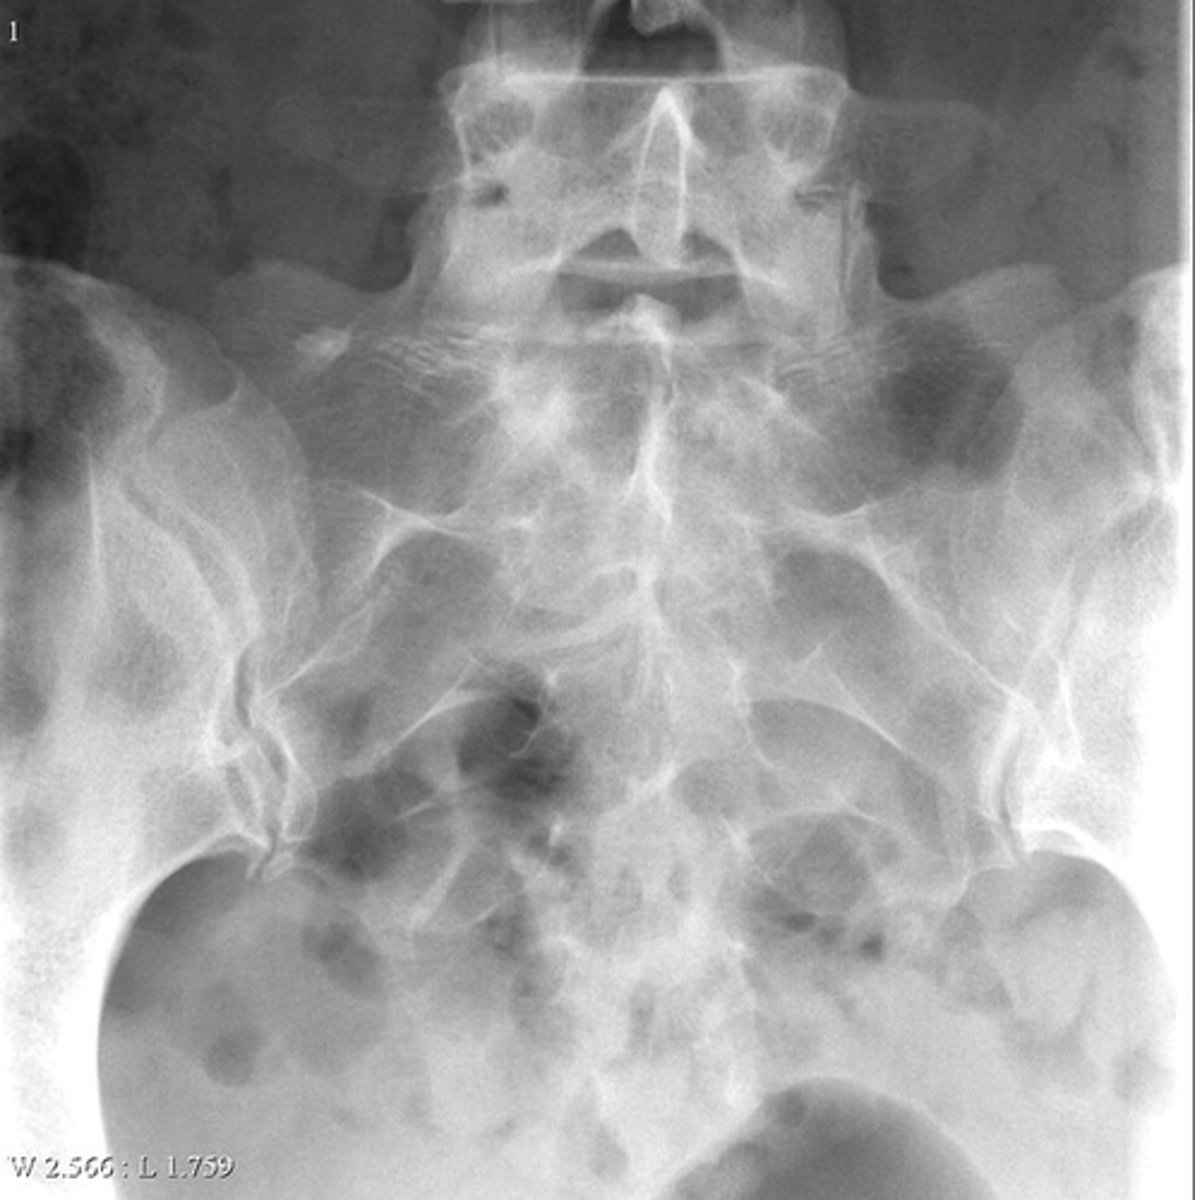

Lateral proximal tibia

Bone

<p>Bone</p>

- Longitudinal: epiphysis/metaphysis (up to joint surface)

- Eccentricity: eccentric

- Transverse: medullary

Location

- Lytic

- Geographic

- Short zone of transition

Behavior

<p>Behavior</p>